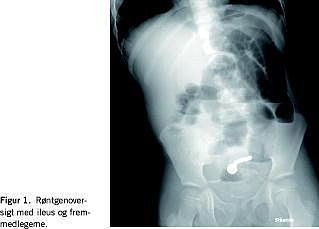

En seks år gammel autistisk dreng blev indlagt med opkastninger og manglende afføring gennem halvandet døgn. Ved den kliniske undersøgelse var han akut smertepåvirket og urolig. Ved abdominal palpation fandtes diffus ømhed og mete-orisme, og ved auskultation hørtes metalliske tarmlyde. Para-klinisk var der let forhøjelse af leukocyttallet til 18 mia./l og normal C-reaktivt protein. En røntgenundersøgelse (oversigt) af abdomen viste tyndtarmsileus og et formentlig metallisk fremmedlegeme i det lille bækken (Figur 1 ).